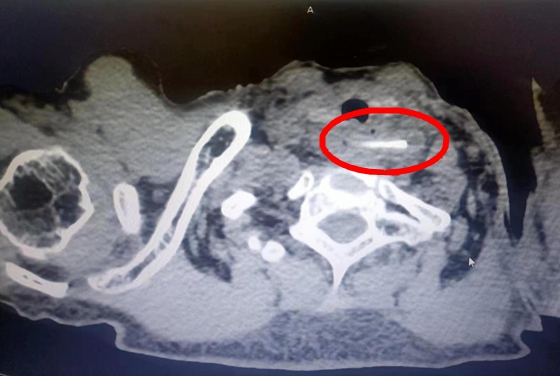

患者CT影像图

2月21日,王奶奶被送入湘雅常德医院消化内科病房。检查后发现,异物不仅横跨患者食道两端且已出现感染,更严重的是,异物的一端已经刺穿左颈总动脉且患者因感染、呕血,已出现休克症状。湘雅名医、消化内科主任张桂英教授迅速判断:患者颈段食管被坚硬的异物戳破,最危险的是戳出去的硬物已经刺入左颈总动脉,加上伤口已经感染,左颈总动脉破口处随患者颈部运动而间断出血,异物随时有断端脱出导致大出血的可能,患者目前情况十万火急,生命垂危!